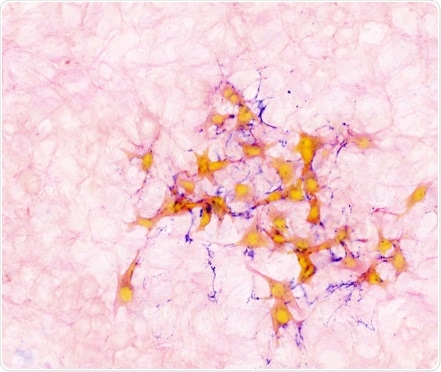

Image showing mouse breast cancer cells (orange) within lung tissue (light pink), connected with protein fibres (purple).

The study, published in Nature Cell Biology, used a mouse model to show that, after cancer cells from a breast tumor arrive in the lungs, a signal sent out from the lung cells causes cancer cells to change shape and grow protrusions that latch onto the lung tissue. The lung cells then protect them within the lung tissue.